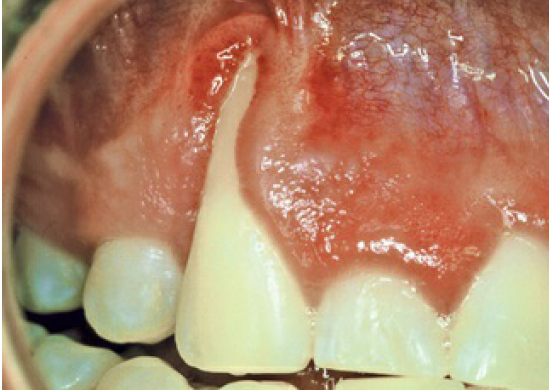

Jau 1960 metais buvo nustatyta, kad periodontas labiausiai kenčia dėl susikaupusių apnašų. Žmogaus burnoje galima aptikti maždaug šeši šimtus rūšių bakterijų: dalis jų neturi neigiamo poveikio sveikatai, tačiau kai kurios bakterijos gali sukelti įvairius negalavimus. Jei nesirūpinama tinkama dantų ir dantenų higiena, ima kauptis apnašos, iš kurių vėliau susiformuoja dantų akmenys. Nors patys dantų akmenys nesukelia periodonto ligų, tačiau jų šiurkšti ir porėta tekstūra sudaro palankesnes sąlygas kauptis bakteriniam apnašui. Ilgainiui tarp dantų ir dantenų atsiranda tarpeliai, kurie vadinami dantenų kišenėmis. Atsiradus šiai patologijai bakterijos ima dar sparčiau daugintis, todėl išsivysto uždegimas, apimantis gilesnius audinius ir žandikaulio kaulą. Ligos eigai įtakos turi imuninė sistema – jei periodontitas nėra laiku gydomas, šis susirgimas didina širdies susirgimų riziką, gali neigiamai paveikti diabeto eigą ar lemti priešlaikinį gimdymą.

Periodontologas visada vertina paciento burnos būklę ir sudaro individualų gydymo planą. Jei nėra diagnozuojami negrįžtami pakitimai, kartais tereikia atlikti profesionalią burnos higieną ir nuvalyti viršdanteninius ir podanteninius akmenis. Jei procesas pažengęs atleikamas giluminis valymas (dantenų kiuretažas) su uždegimo pažeistų dantenų konservatyviu pašalinimu. Ypatingai sunkiais atvejais atliekama atliekama lopo operacija, kai pašalinamas didelis kiekis pažeistų dantenų, žandikaulio defektai gali būti užpildomi kaulo užpildais. Šiuolaikinė periodontologija užtikrina, kad pacientui atliekamos procedūros nesukels pernelyg didelio diskomforto – visuomet yra taikomas nuskausminimas.